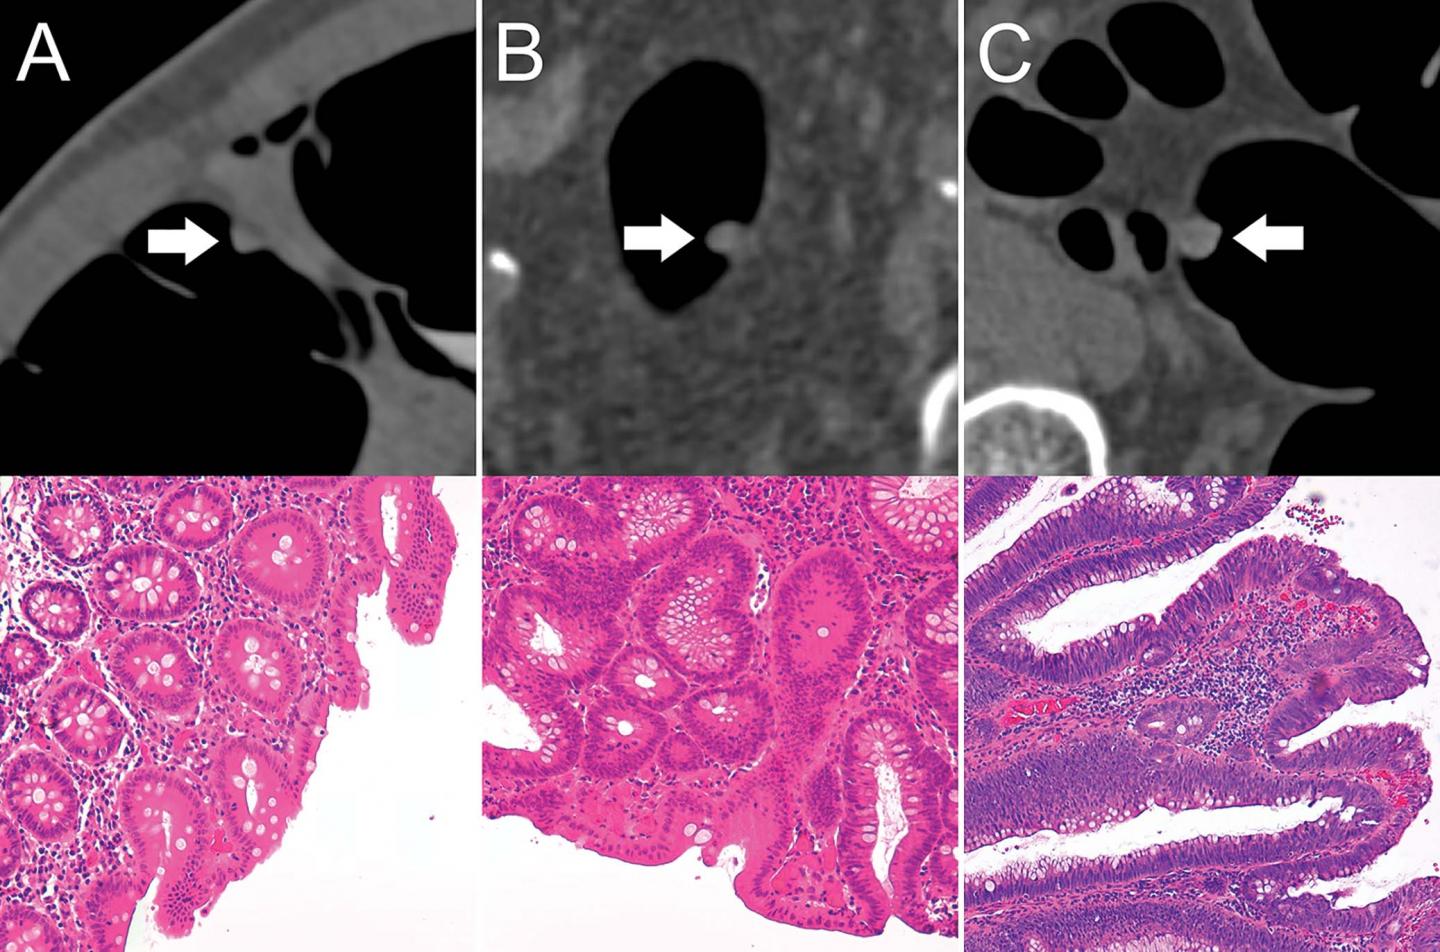

OAK BROOK, Ill. - A machine learning algorithm helps accurately differentiate benign and premalignant colorectal polyps on CT colonography scans, according to a study published in the journal Radiology .

During the last two decades, CT colonography emerged as a noninvasive alternative to colonoscopy in screening for colorectal cancer. It is comparable to colonoscopy in detecting most polyps and is effective at visualizing portions of the colon that in cases of complex anatomical conditions cannot always be evaluated by colonoscopy. However, CT colonography does not enable a definite differentiation between benign and premalignant polyps, which is crucial for individual risk stratification and therapy guidance.

For the new study, researchers leveraged the power of radiomics, a process of extracting quantitative features from medical images, to characterize polyps beyond what was apparent to the naked eye.

The researchers developed a machine learning algorithm to predict the character of the individual polyps based on quantitative image features extracted through radiomics. They applied the noninvasive, radiomics-based machine learning method on CT colonography images from a group of asymptomatic patients at average risk of colorectal cancer. The machine learning algorithm was trained on a set of more than 100 colorectal polyps in 63 patients and then tested on a set of 77 polyps in 59 patients.

In the test set, the machine learning approach enabled noninvasive differentiation of benign and premalignant CT colonography-detected colorectal polyps, with a sensitivity of 82%, and specificity of 85%. The area under the curve (AUC), a graphical measurement that reflects how much the model is capable of distinguishing between benign and precancerous polyps, was excellent.

"These results serve as proof-of-concept that machine learning-based image analysis allows the noninvasive differentiation of benign and premalignant colorectal polyps in CT colonography data sets," said study lead author Sergio Grosu, M.D., radiologist from University Hospital, Ludwig Maximilian University of Munich, in Munich, Germany. "The AUC of 0.91 indicates that this method works well."